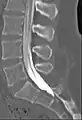

Myelography

Myelogram showing arachnoiditis in the lumbar spine.